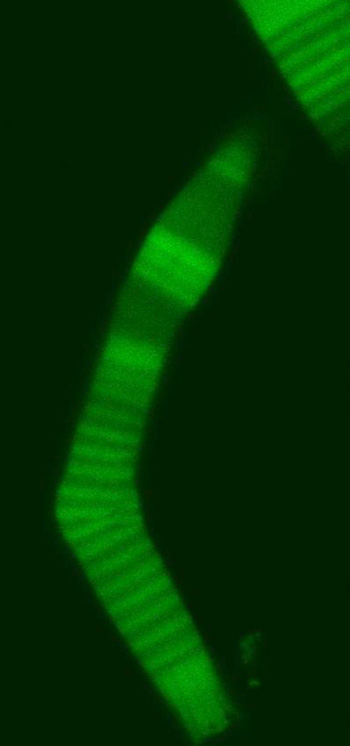

![]() |

| SUNY Cortland Assistant Professor of Physics Aphrodite Ahmadi's study encompassed the basics of eye rod flexibility. This genetically fragile rod is shown bending as it begins to fail. The above left image, which details the rods bending, appeared in the Biophysical Journal and is reproduced here with the journal's permission. |

When looked at under a microscope, the rod photoreceptor cells in a tadpole eye appeared to gradually bend into a crook like a boomerang and break. Eventually, the rods no longer will transfer visual information to the brain.